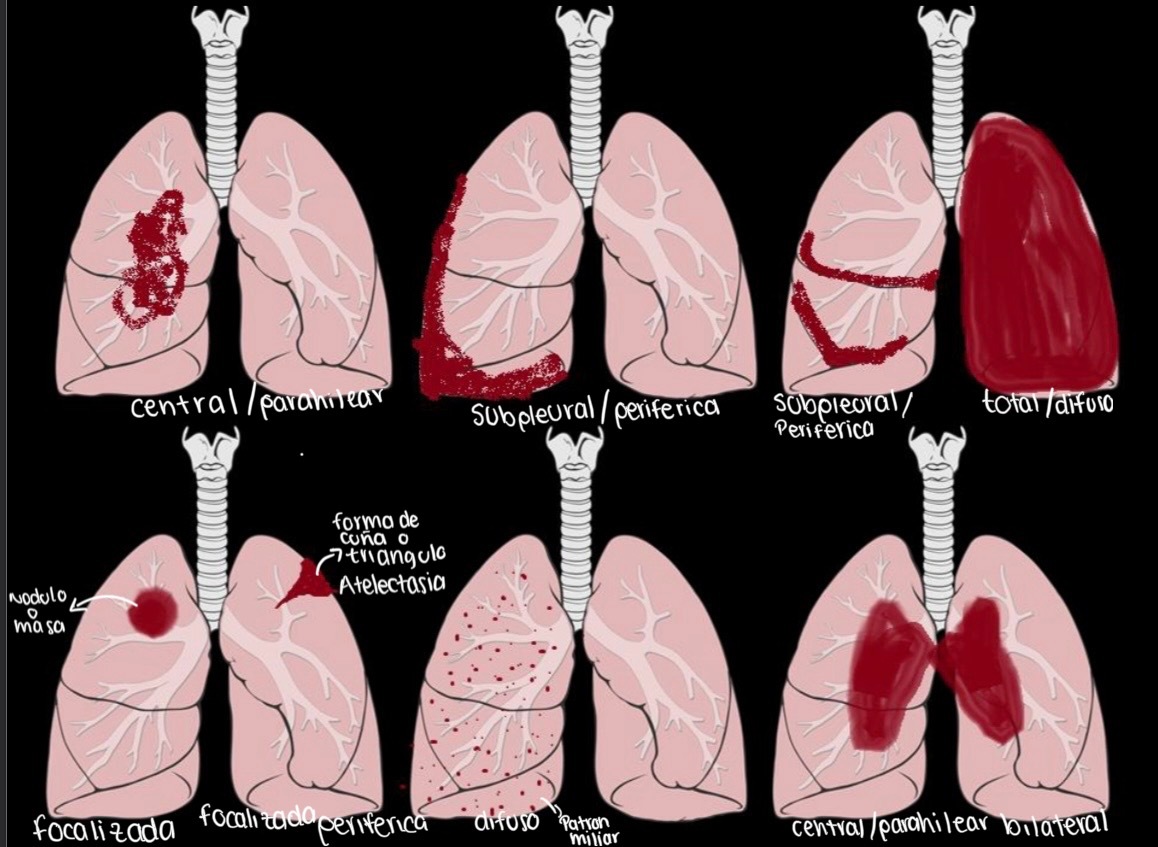

tipos de distribución en los patrones pulmonares (6)

A

• central/parahilear

• subpleural/ periférica

• total/difusa

• focalizada

• focalizada periferica

• central/parahilear bilateral